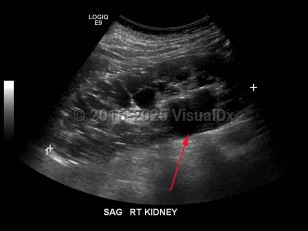

Hydronephrosis

Renal calculus

Polycystic kidney diseasePolycystic kidney disease

Pyelonephritis